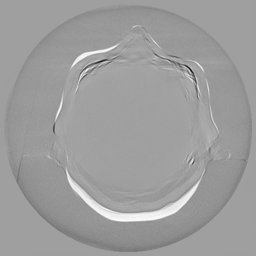

III-C Uncertainty analysis

Classical diffusion models reconstruct images by progressively denoising from an initial Gaussian noise image, a process that inherently introduces uncertainty due to random noise initialization. In contrast, I2SB directly learns a diffusion bridge between two sample distributions, effectively bypassing the need for random noise sampling and thereby reducing reconstruction variability.

To assess the uncertainty of our method, we performed multiple reconstructions using different random seeds. As shown in Fig. 3, the ground truth and representative sampled images are presented in Fig. 3(a) and (b–d), respectively. The mean reconstruction and pixel-wise standard deviation across runs are displayed in Fig. 3(e) and (f). Only minimal differences are observed between reconstructions, indicating that I2SB produces highly consistent results. These findings confirm that, compared with classical diffusion models, I2SB substantially reduces uncertainty across repeated reconstructions.